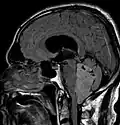

Les épendymomes supratentoriels (SE) représentent entre 40 % et 60 % des tumeurs intracrâniennes. Localisées au niveau supratentoriel, ces tumeurs apparaissent comme des grosseurs peu homogènes, présentant des zones kystiques, des calcifications mais également des zones hémorragiques et nécrosées.

Aspect radiologique à l’IRM en séquence T1 après injection de Gadolinium d’un épendymome supratentoriel, caractérisé par une lésion bien délimitée du lobe frontal gauche avec prise de contraste hétérogène et des zones de nécrose.